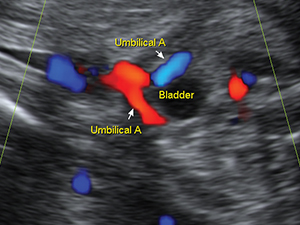

Abdomen